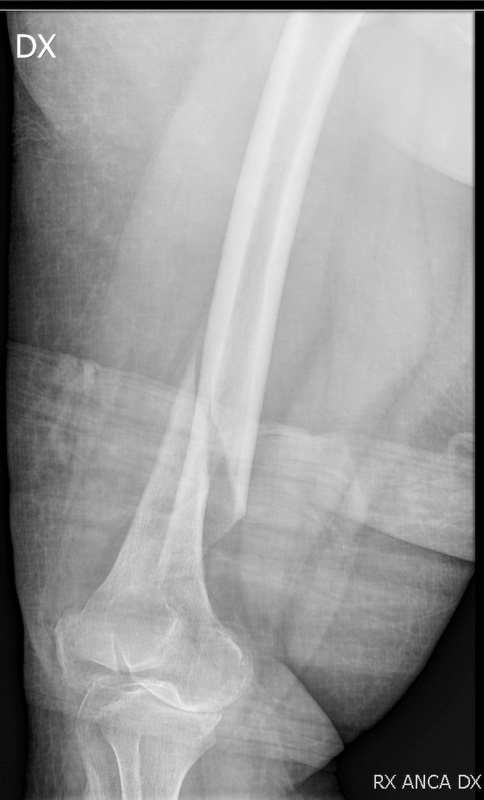

Le radiografie dell’intera estremità, esami di primo livello, devono comprendere le articolazioni prossimali e distali alla lesione sospetta; nei casi di politraumi severi le radiografie devono essere eseguite appena i pazienti sono emodinamicamente stabili, al fine di confermare e caratterizzare la frattura. La Tac, con le più moderne ricostruzioni tridimensionali, rappresenta un esame di secondo livello, ma allo stesso tempo spesso necessario. Infatti le fratture distali di femore, per la loro frequente complessità e per il frequente coinvolgimento articolare, richiedono uno studio approfondito che possa condurre a una efficace valutazione del coinvolgimento articolare e anche a una valutazione prognostica specifica. Al momento della pianificazione del trattamento, infatti la TC con ricostruzione coronale e sagittale è raccomandata per le fratture complesse, quelle con estensione intra-articolare e per la valutazione dei frammenti osteocondrali 5. La TC è fortemente raccomandata per valutare la frattura di Hoffa, che è una frattura intra-articolare del femore distale sul piano coronale che coinvolge più comunemente il condilo laterale, con un’incidenza del 38,1%. Nei casi di Damage control è necessario eseguirla dopo il posizionamento del fissatore esterno.

L’utilizzo delle placche ha visto il progressivo abbandono delle Lame-Placca a stabilità fissa ovvero placche angolate di 95 gradi che forniscono una fissazione stabile controllando l’allineamento in 3 piani, e di difficile applicazione, per far spazio alle placche DCS, e sempre più recentemente alle placche LISS (“Less Invasive Stabilization System”). Si tratta di placche modellate anatomicamente preconformate che offrono la versatilità aggiuntiva di opzioni di fori distali multipli per le viti, combinate con la possibilità di comprimere i frammenti e conferire stabilità angolare. L’applicazione inoltre si può ottenere con una tecnica meno invasiva, con tecnica a scivolamento (MIPO). Le guide di allineamento infatti consentono il posizionamento percutaneo delle viti prossimali 9 (Fig 2. A-B).